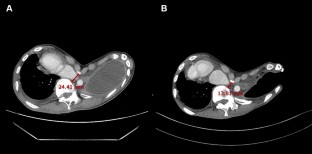

A 27-year-old man with severe pectus excavatum, dextrocardia and spinal scoliosis underwent thoracoscopic pleural decortication due to failure of 1-month medical treatment for tuberculous empyema. One month after the pleural decortication, he again underwent open thoracostomy window for repetitive pleuro-cutaneous fistula with tuberculosis empyema. He was subsequently referred to our clinic for progressive dyspnea and bilateral leg edema 4 months after the open thoracostomy window. Evaluations revealed deterioration of the chest wall depression and further compression of the inferior vena cava, which were considered an aggravation of the pectus excavatum after the open thoracostomy window. Herein, we present an extremely rare case of deterioration of chest wall depression causing congestive hepatopathy after an open thoracostomy window in a patient with pectus excavatum and tuberculosis empyema.

Fig. 2